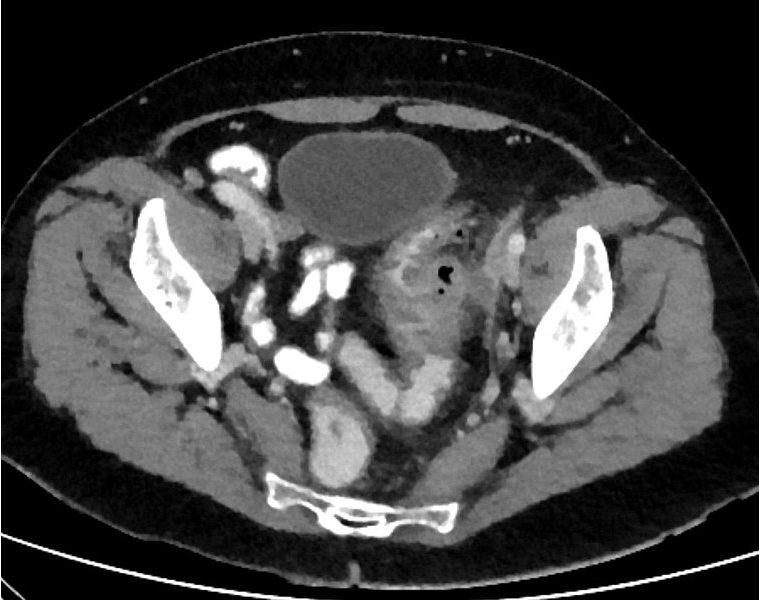

Le seul examen nécessaire au diagnostic est le scanner abdominopelvien avec injection qui confirmera le diagnostic, permettra d’identifier une éventuelle complication et guidera la thérapeutique.

L’opacification basse n’est pas nécessaire, elle n’apportera pas d’élément supplémentaire.